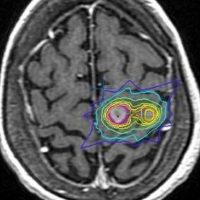

定位放射線治療のイメージ:ピンポイントとはいえない

近接する2つの転移巣への定位放射線治療です。右側は放射線治療計画の等線量曲線といいます。5回に分けて25グレイの放射線治療を行います。

転移性脳腫瘍は,画像で見えているところよりも少し周囲の脳へ浸潤しています。ですからガンマナイフでもサイバーナイフでもリニアックでも,見えている腫瘍 GTVよりも,PTVがやや広めになります。どういうことかというと,脳転移にピンポイントで放射線をかけるというのは,ある意味では「ウソ」で,周囲の脳は必ず被曝します。ガンマナイフでもサイバーナイフでも同じことです。